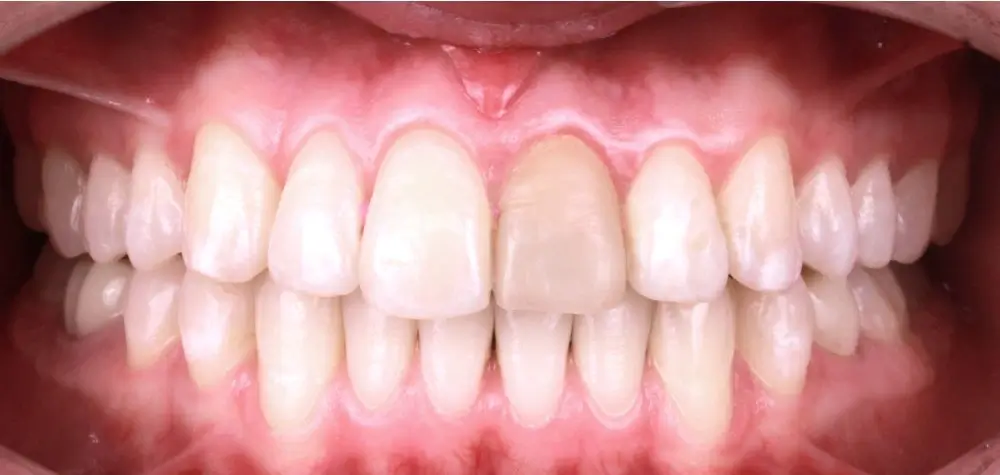

Кейс 9

Бирковская Екатерина Александровна

Количество кап ВЧ 23

Количество кап НЧ 23

ДО

ПОСЛЕ